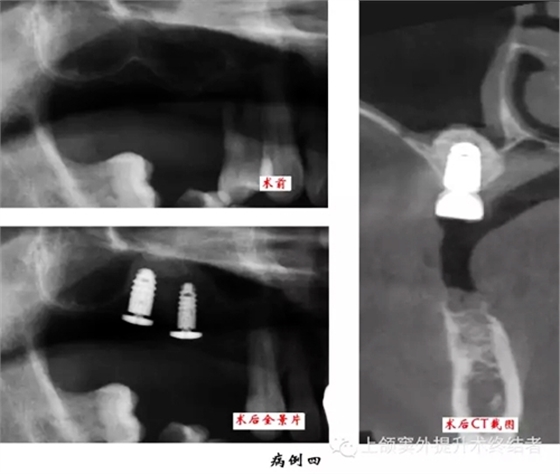

術(shù)前檢查口腔內(nèi)情況,主要包括骨和粘膜的狀況。拍攝曲體層片,測量并按其放大率計數(shù)上頜竇底至牙槽嵴頂?shù)木嚯x,檢查上頜竇形態(tài)和密度,排除無癥狀的上頜竇慢性炎癥或囊腫等。觀察竇內(nèi)有無上頜竇橫隔,位置是否影響手術(shù)操作,如有影響則需調(diào)整開窗位置。拍攝直線體層片和上頜竇矢狀面體層片可以顯示上頜竇底斷面或矢狀面的現(xiàn)狀,但以上圖像都有一定程度的放大失真。如有條件采用三維螺旋CT進行掃描可以準確測量上頜竇底至牙槽嵴頂?shù)膶嶋H距離,觀察上頜骨形態(tài),分析術(shù)區(qū)條件和檢查上頜竇健康狀況,以利于進行術(shù)前診斷和制定治療計劃。上頜竇底提升同期種植術(shù)前應(yīng)制作手術(shù)模板。